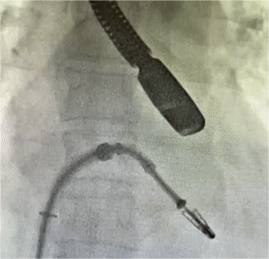

手术过程中,团队在食道超声和DSA引导下,经皮经股静脉建立路径,并穿刺房间隔,瓣膜夹通过输送系统送入左心房,顺利到达病变二尖瓣区域。由于患者返流的机制为功能性返流,瓣环扩大且后叶长度不到10mm,给手术带来考验。在精确评估二尖瓣反流位置、抓捕位置、反流程度,郭延松教授团队精细选定夹持位置,巧妙夹合。患者术后反流程度从重度转至微量,手术取得圆满成功。

▲二尖瓣瓣膜夹释放